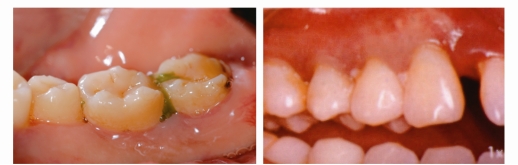

食物嵌塞

牙周炎症导致牙龈萎缩、牙缝增大,食物嵌塞也就随之而来。